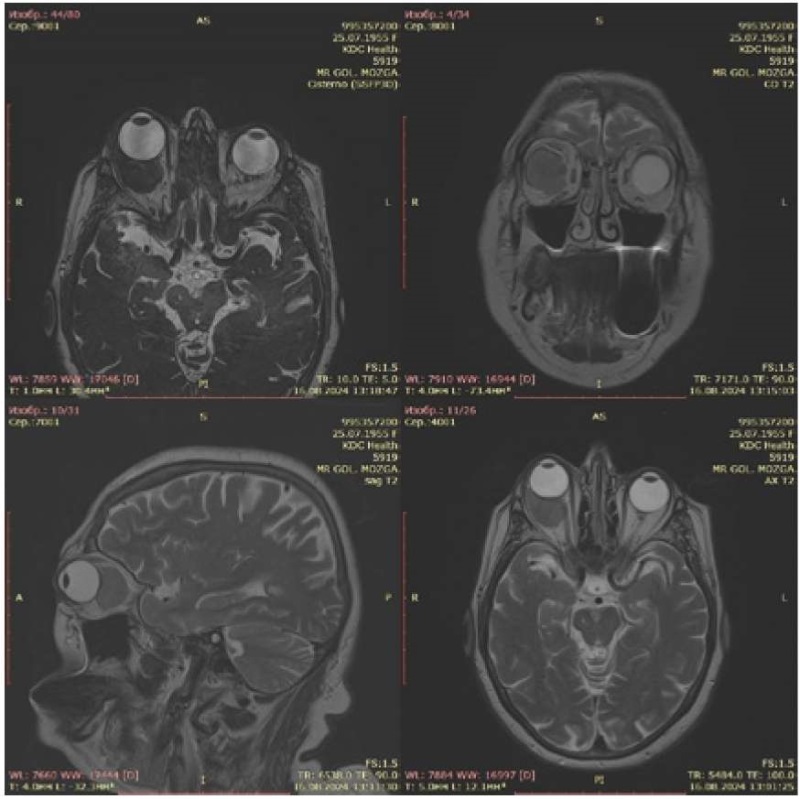

В связи с выявленными нарушениями глазодвижения пациентка направлена на консультацию невролога. В неврологическом статусе: неполный синдром верхнеглазничной щели справа (парез ветвей глазодвигательного нерва, экзофтальм, мидриаз). Рассеянная микроочаговая симптоматика в виде положительных рефлексов орального автоматизма, равномерного, симметричного, оживления сухожильных рефлексов с расширением рефлексогенных зон. Двигательных, чувствительных, координаторных и тазовых нарушений выявлено не было. После изучения клинико-анамнестических данных направлена на магнитно-резонансную томографию (МРТ) головного мозга для исключения новообразования крыла клиновидной кости (рис. 2.)

Рисунок 2. Ретробульбарное образование правой глазницы

Figure 2. Retrobulbar formation of the right orbit

Заключение МРТ от 16.08.2024: МРТ-признаки ретробульбарного образования правой глазницы, умеренной диффузной кортикосубкортикальной атрофии поверхности больших полушарий, умеренной дилатации конвекситальных субарахноидальных ликворных пространств, полушарных очагов глиоза дистрофического генеза (микроангиопатия Fazekas gr. 2), постишемических глиозных изменений в левой височной и правой теменных долях.